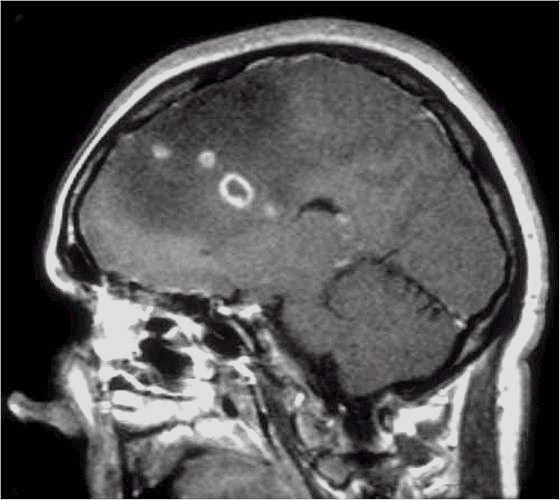

Glioma

ad alto grado di malignità (Glioblastoma) |

Lesioni caratterizzate da un accrescimento veloce con infiltrazione del tessuto cerebrale attiguo e diffusione a distanza di cellule maligne.

Scopo della chirurgia è ridurre macroscopicamente la massa tumorale per facilitare ulteriori trattamenti (principalmente radio - chemioterapia mentre altri protocolli terapeutici sono ancora in fase di studio).

In queste lesioni la loro conformazione anatomica, praticamente sempre di tipo II (Daumas-Duport) non ha un ruolo così dirimente nell'indicazione chirurgica poiché il comportamento biologico è sicuramente il fattore più importante.

RM:

glioma con segni di trasformazione maligna